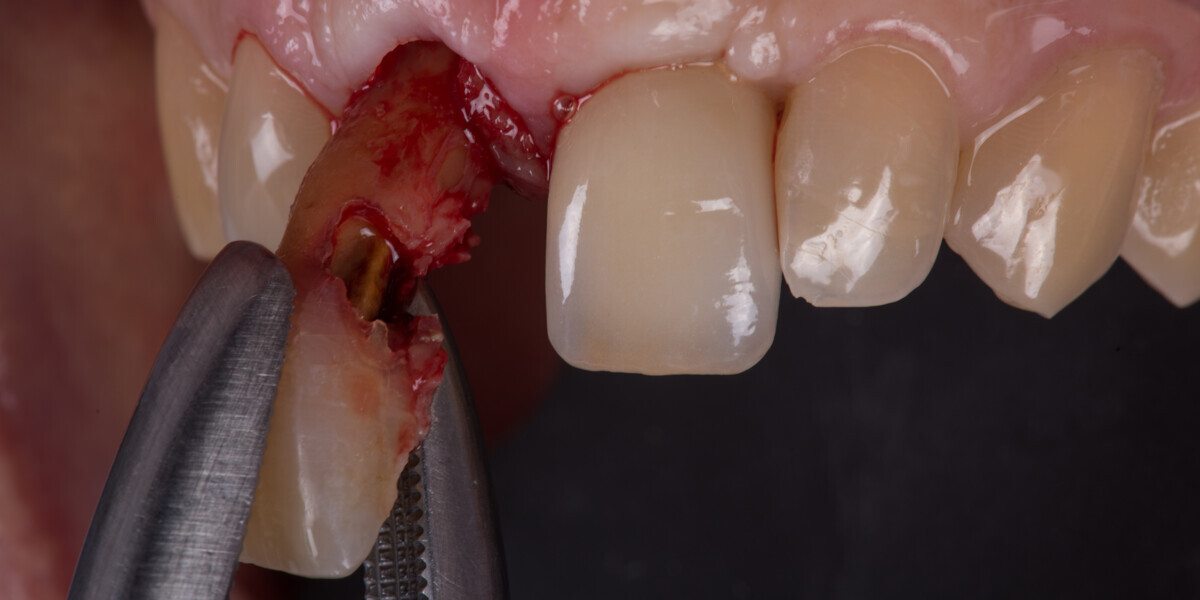

Immediate placement and restoration of a Straumann BLX implant replacing maxillary incisors